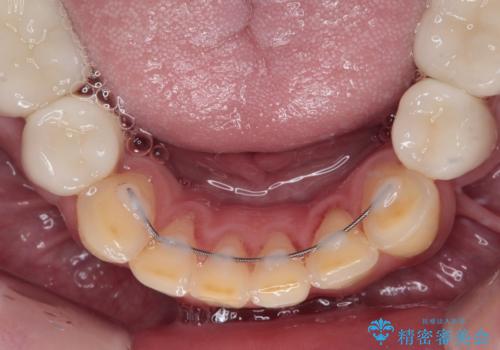

当初はほとんどの歯をむし歯治療のようにオールセラミッククラウンにて補綴治療を行う予定でしたが、仮歯に置き換えた時点で、口元の突出感や下顎前歯の叢生が気になるとのことで、上下左右の第一小臼歯4本を抜歯したワイヤー装置での抜歯矯正を行うこととしました。

矯正治療終了後に、残った歯をオールセラミッククラウンにて補綴治療を行うこととしました。